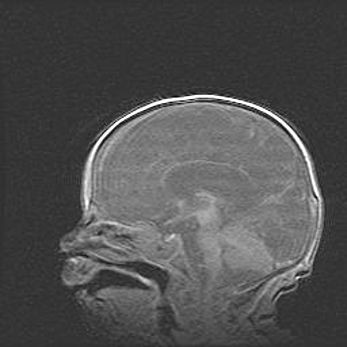

Мальформация Денди-Уокера. Киста задней черепной ямки.

Агенезия мозолистого тела.

Возраст: 2,5 месяца

Вес: 2420 г

Пол: женский

Окружность головы: 37 см

Срок гестации: 32 недели

Мальформация Денди—Уокера — редкий вид патологии ЦНС, представляющий собой врожденный порок развития каудального отдела ствола и червя мозжечка, ведущий к неполному раскрытию срединной (Мажанди) и латеральных (Лушка) апертур IV желудочка мозга. Для этогно синдрома характерна триада симптомов: гипотрофия червя мозжечка и/или полушарий мозжечка, кисты задней черепной ямки, гидроцефалия различной степени. В 70% случаев порок сочетается и с другими аномалиями головного мозга, в частности с агенезией мозолистого тела.